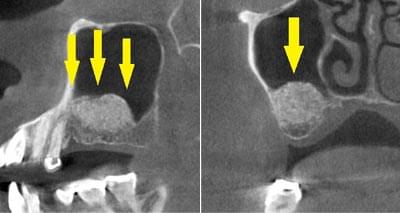

患者様のインプラント治療前のレントゲン写真です。右下顎大臼歯2本の抜歯後のレントゲン写真で、写真の黄色矢印は、歯の周囲の歯槽骨が大きく吸収されてしまっていました。

写真のように、CTで見ると、骨吸収の様子が良く分かり、下顎骨の中を通る神経近くまで骨がありませんでした。

さらに、CTで、別な方向から見ると、黄色矢印のように骨が吸収されていて、緑色矢印で示される神経の通る管に迫り、インプラントが埋入できるような骨量はありませんでした。

インプラントを埋入するために、骨を増やす方法はいくつかありましたが、この場合、患者様ご自身の骨をブロック状で移植するのが最も適していると判断し、自家骨移植術を行ないました。患者様ご自身の下顎前歯の下方から骨を採取して、骨がなかった部位に移植し、スクリューで固定したCT画像です。黄色矢印部分が、2つの骨片を移植して、固定したところです。

手術後の、別な方向からみたCT画像です。術前に大きく吸収されていた部分に、骨のブロックが移植され、骨が造成されています。真っ白にピンのように写るのは、骨を固定した小さなスクリューです。